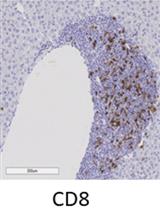

Immune cell infiltration, particularly cytotoxic CD8α lymphocyte infiltration, plays an important role in development of diabetic nephropathy. Although CD8α infiltration can be evaluated by its production of cytokines, its localization in the kidney is of particular importance. The current protocol describes CD8α immunostaining using a Vectastain ABC kit. This protocol works well with most commercially available antibodies, including CD8α antibodies in kidneys of diabetic mice.

Diabetic nephropathy (DN), a complication of diabetes, is the most common cause of end-stage renal disease. Pathological changes in DN are closely correlated with the degree of renal immune cell infiltration, particularly toxic CD8α lymphocyte infiltration. Therefore, a sensitive and reliable method to localize CD8α lymphocytes in the kidney will facilitate the research in diabetic nephropathy as well as other fields relating inflammation (Li et al., 2018).